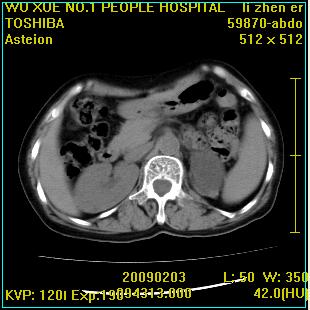

标题: CT18564:女,57岁,无不适,体验B超提示肾积水等 [打印本页]

标题: CT18564:女,57岁,无不适,体验B超提示肾积水等

左肾及左输尿管上端结石,左肾重度积水并左肾萎缩(不排除左肾先天性发育不良)。

左输尿管上端结石,左发育不良性多囊肾并积水;

右肾代偿性增大并肾盂积水,脾大。

左肾及左输尿管上端结石,基本上丧失肾功能了。

左肾改变考虑先天发育不良

此患都左肾呈囊性变,边缘有高密度钙化,还是考虑结核吧.